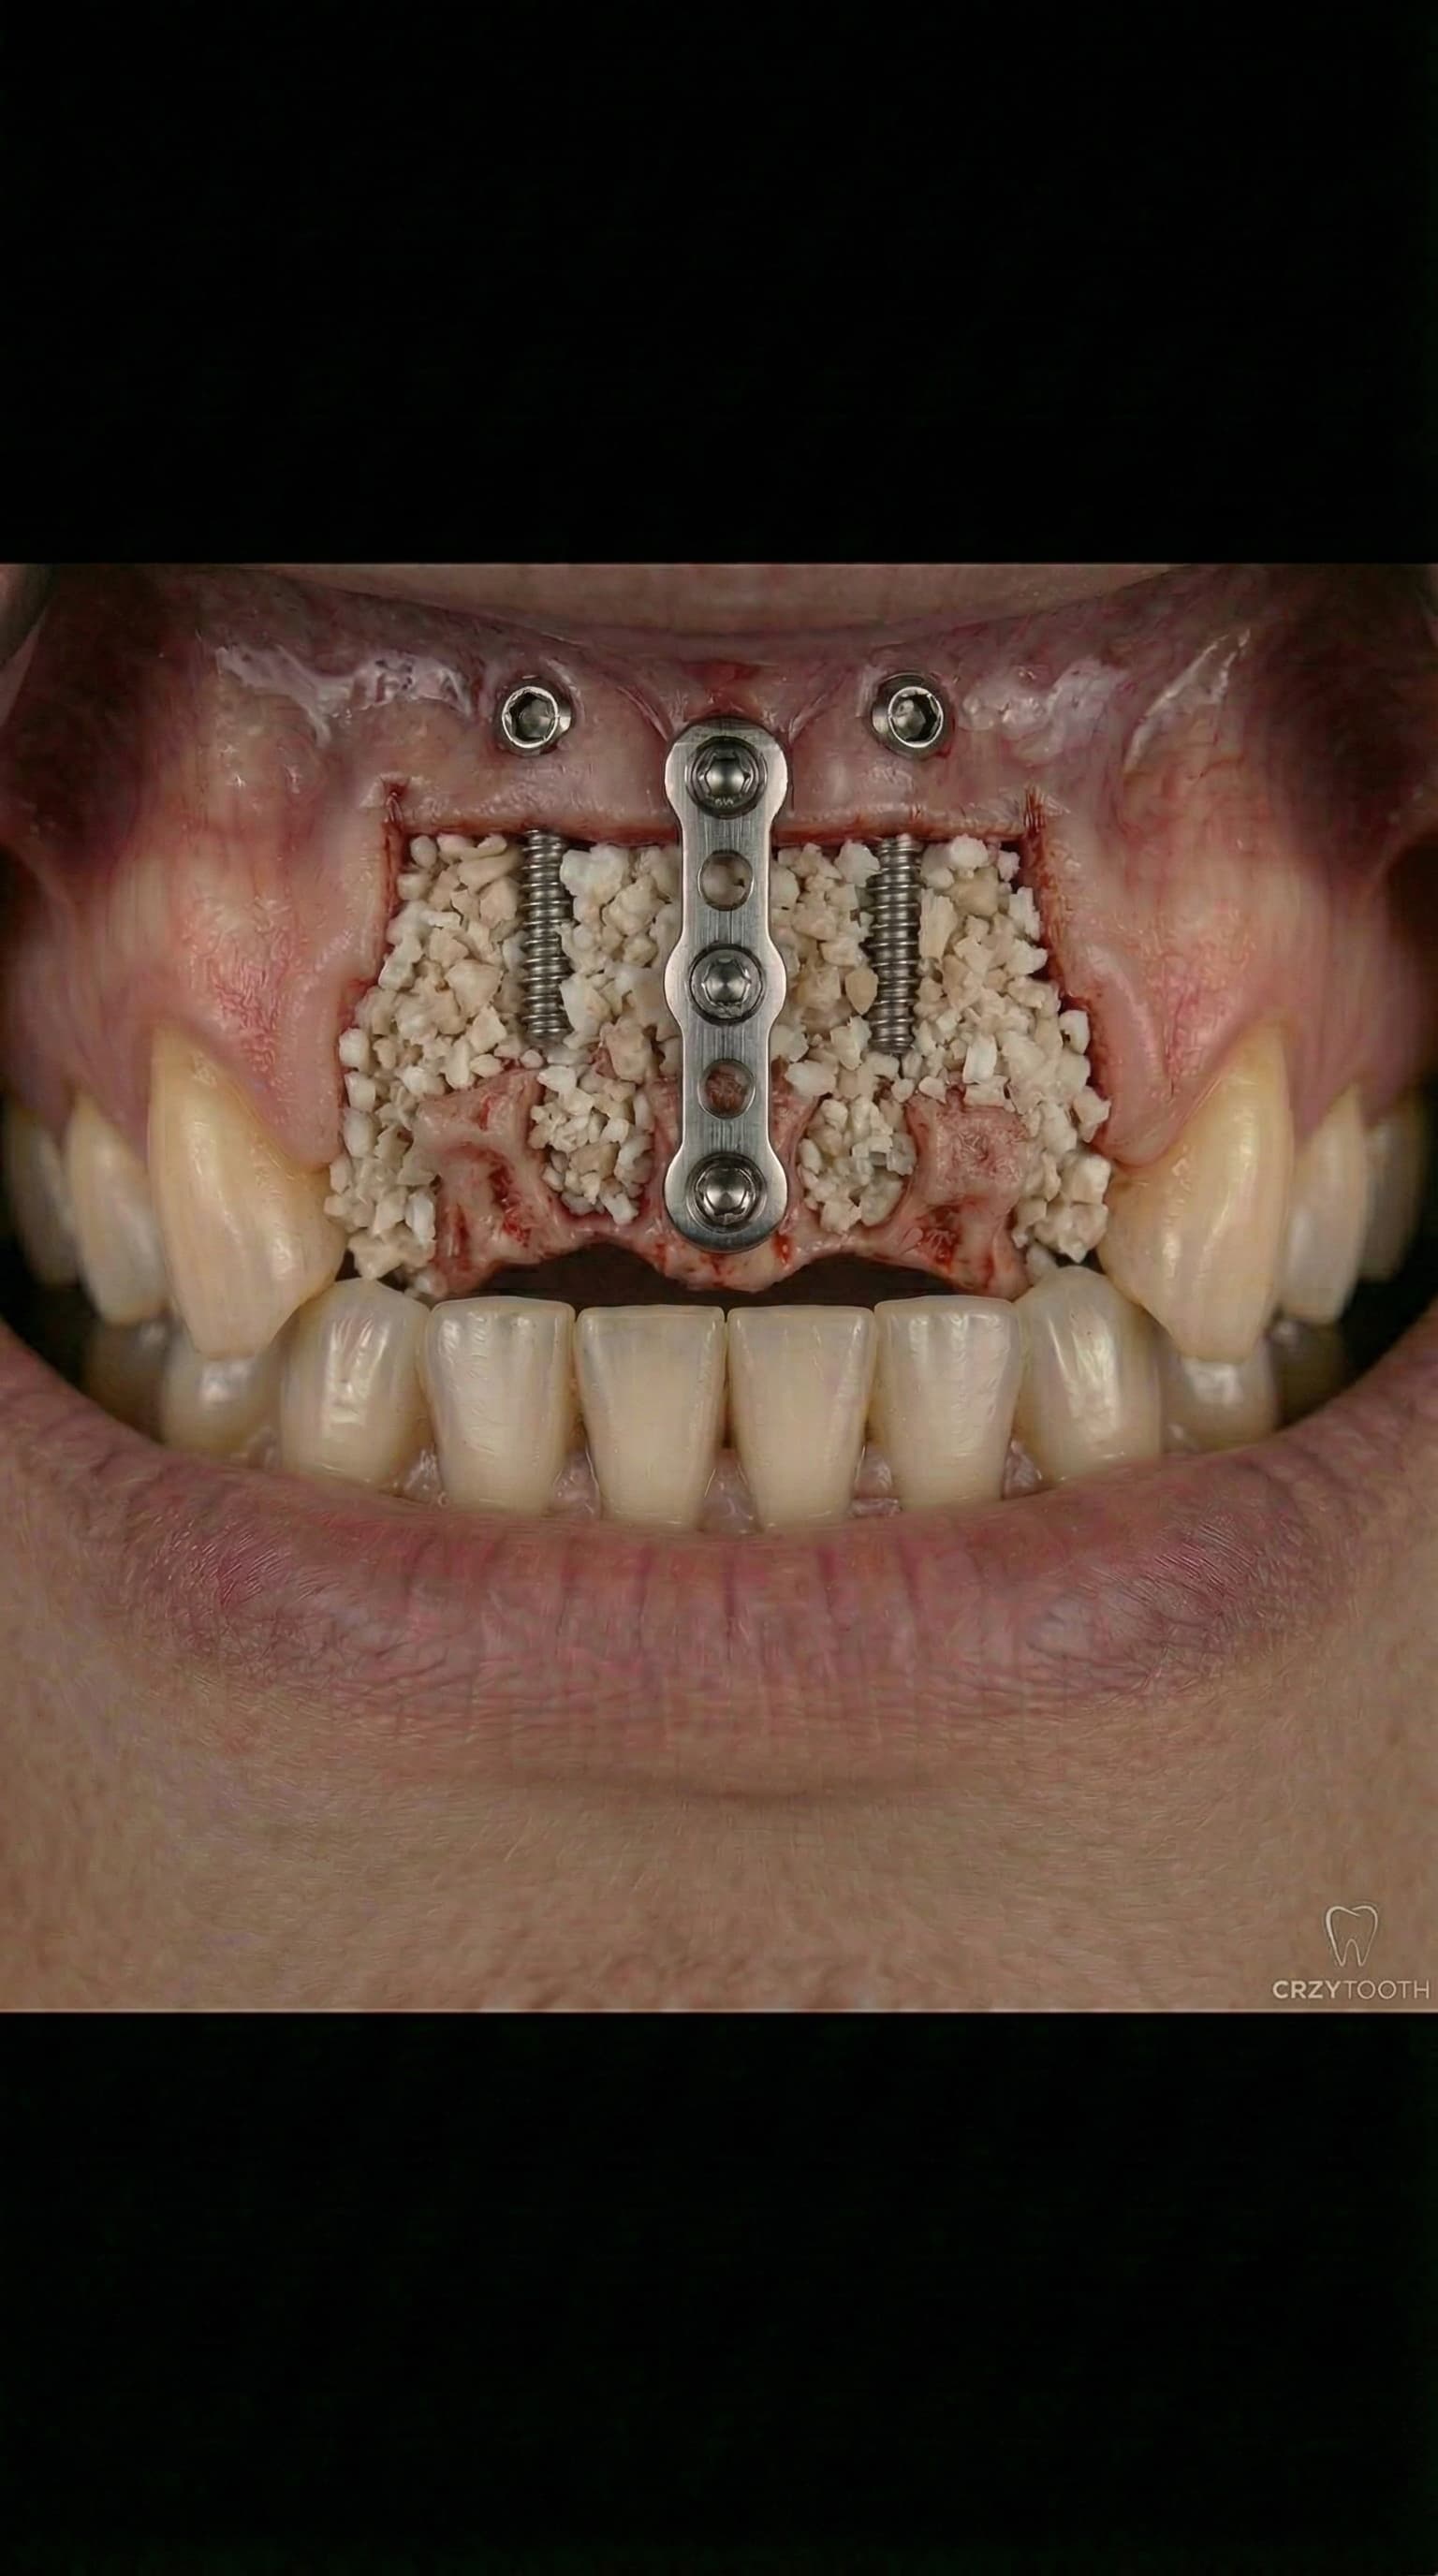

Bone Grafting & Sinus Lifts

Advanced bone regeneration using organic and holistic bone grafting materials to rebuild jawbone lost to tooth extraction, periodontal disease, or trauma. Dr. Antipov performs sinus lift surgery (sinus augmentation), ridge augmentation, socket preservation, block bone grafts, and guided bone regeneration (GBR). We offer autogenous (your own bone), allograft, xenograft, and synthetic bone graft options — including minimally processed, naturally derived materials for patients who prefer a holistic approach to dental implant preparation.

Organic & Holistic Bone Grafting

For patients who prefer a natural approach, Dr. Antipov offers organic and holistic bone grafting options using minimally processed, naturally derived materials. From autogenous bone grafts to biocompatible allograft and xenograft materials, we match the bone regeneration technique to your body and your values — without compromising clinical outcomes.